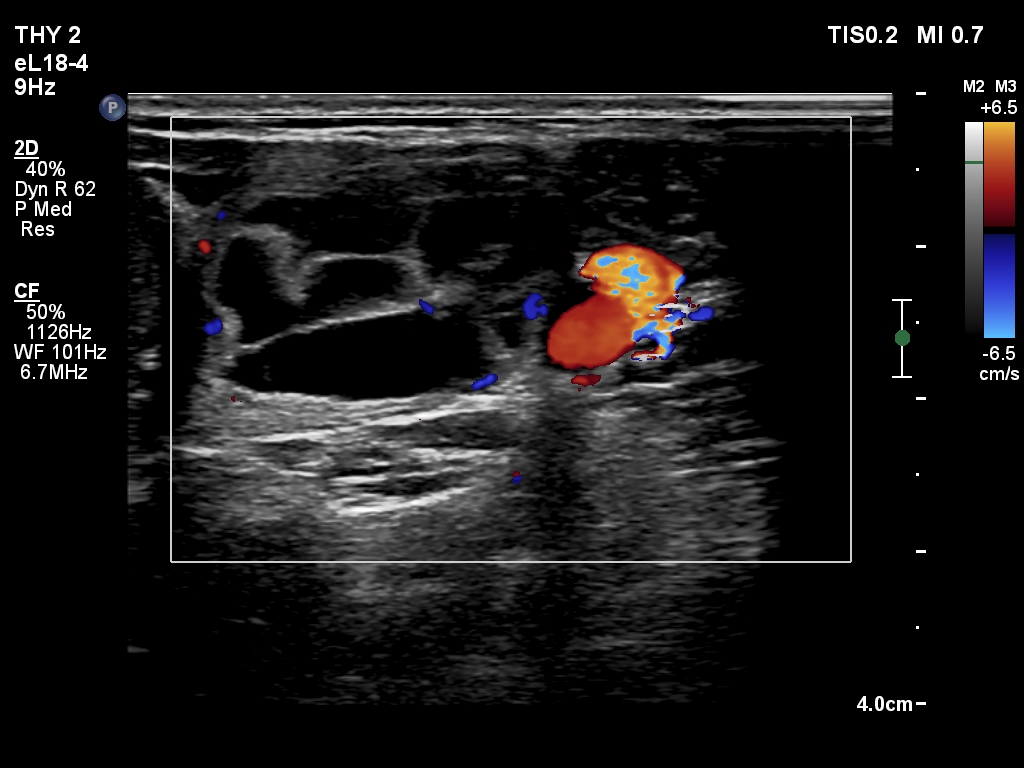

First examination (first and second rows of images):

Clinical presentation: A 25-year-old woman requested evaluation of a neck lump which was discovered by herself 3 weeks ago.

Palpation: an elastic nodule in the left lobe.

Result of blood test: TSH 1.43 mIU/L.

Ultrasonography. The thyroid was echonormal. There was a dominantly cystic nodule in the left lobe. The lesion had echonormal solid area.3.5 mL brown fluid was aspirated. The cyst has begun to refill during the aspiration of the cystic content. Cytology resulted in benign cystic lesion.